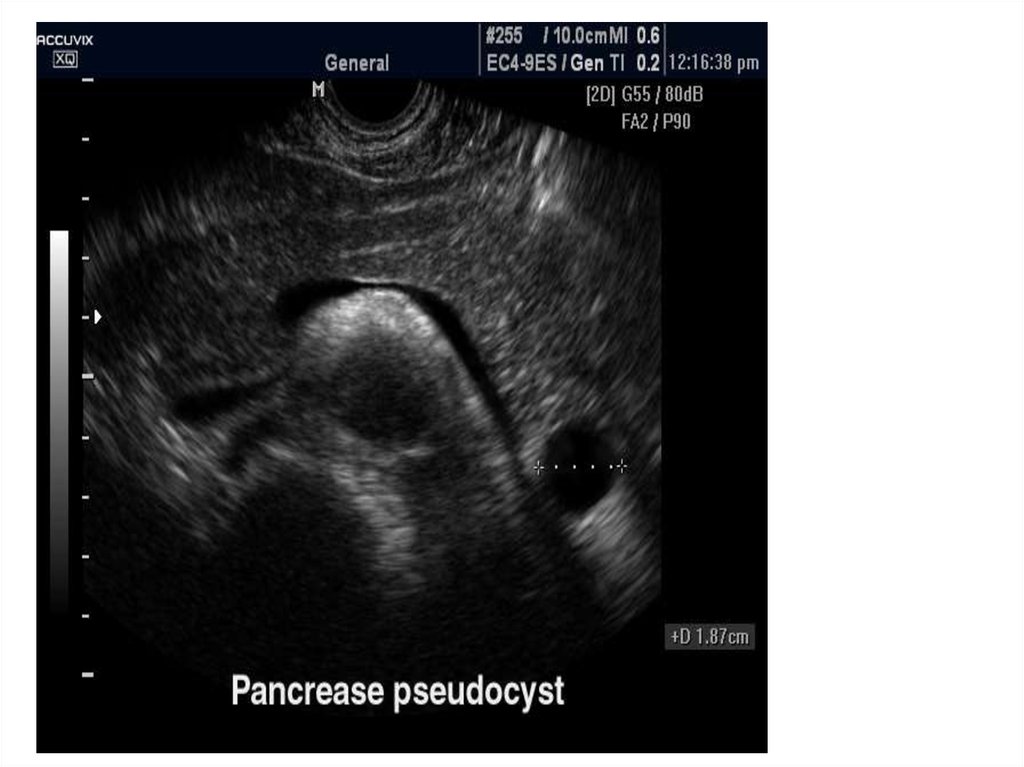

При госпитализациях многократно

выполнялись следующие исследования:

Фиброгастродуоденоскопия

Фиброколоноскопия

Ирригография

УЗИ брюшной полости (киста тела

pancreas 2,0 см)

УЗИ брюшной полости с дуплексным

сканированием

Источник кровотечения выявлен не был